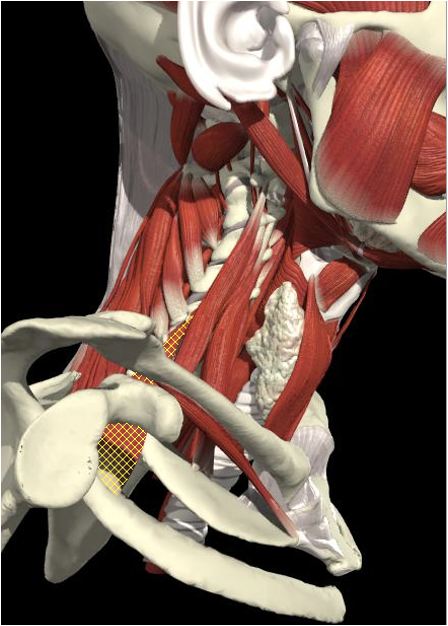

Structures to Avoid

Nerves in Posterior Triangle

Accessory nerve

Lies on LS, enters 1cm cranial to EP posterior border of SCM and runs on line to between middle and lower third of trapezius.

Should inject splenius and levator over 1cm above EP

Cervical plexus cutaneous branches

Mid point of posterior border

Inject levator above this point

Landmarks

Cervical plexus

Midpoint of SCM (EP)

Middle and lower third of Trapezius